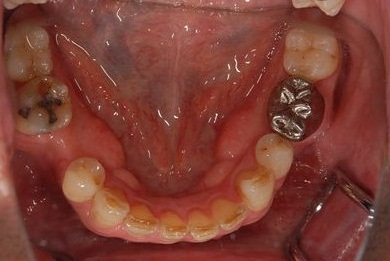

| 性別/年齢 | 男性 / 37歳 | ||||||||||||||||||||||||||||||||

| 主訴 | 前歯(2本)の欠けの治療 | ||||||||||||||||||||||||||||||||

| 治療方針 | 右下欠損部分をインプラント治療にて、機能的・審美的回復を行う。 | ||||||||||||||||||||||||||||||||

| 治療内容 | インプラント1本、メタルボンドセラミッククラウン1本 | ||||||||||||||||||||||||||||||||

| 総治療費 | 252,000円 | ||||||||||||||||||||||||||||||||

| 治療期間 | 7ヶ月 |